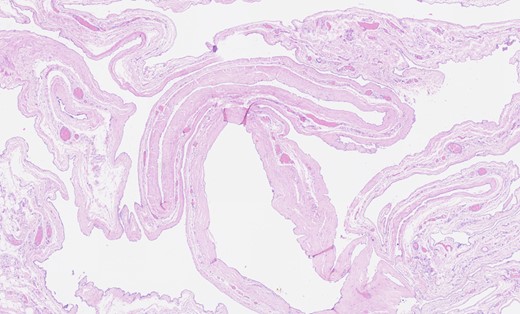

Macroscopic examination of the surgical specimen revealed an atrophic testis 40 × 30 × 30 mm3 with a large, multiloculated structure adherent to it composed of cysts of varying sizes containing serous fluid ~60 mm in maximal dimension (Fig. 2). Histological findings confirmed the presence of numerous thin-walled cysts lined by cuboidal mesothelial cells separated by delicate fibrous stroma. No atypia, mitoses or necrotic regions were observed (Fig. 3). Immunohistochemistry was undertaken and mesothelial cells were positive for WT-1 and calretinin (Figs 4 and 5) and negative for desmin in keeping with a diagnosis of BMM (Fig. 6).

Haematoxylin and eosin staining showing thin-walled cystic areas lined by cuboidal mesothelial cells.